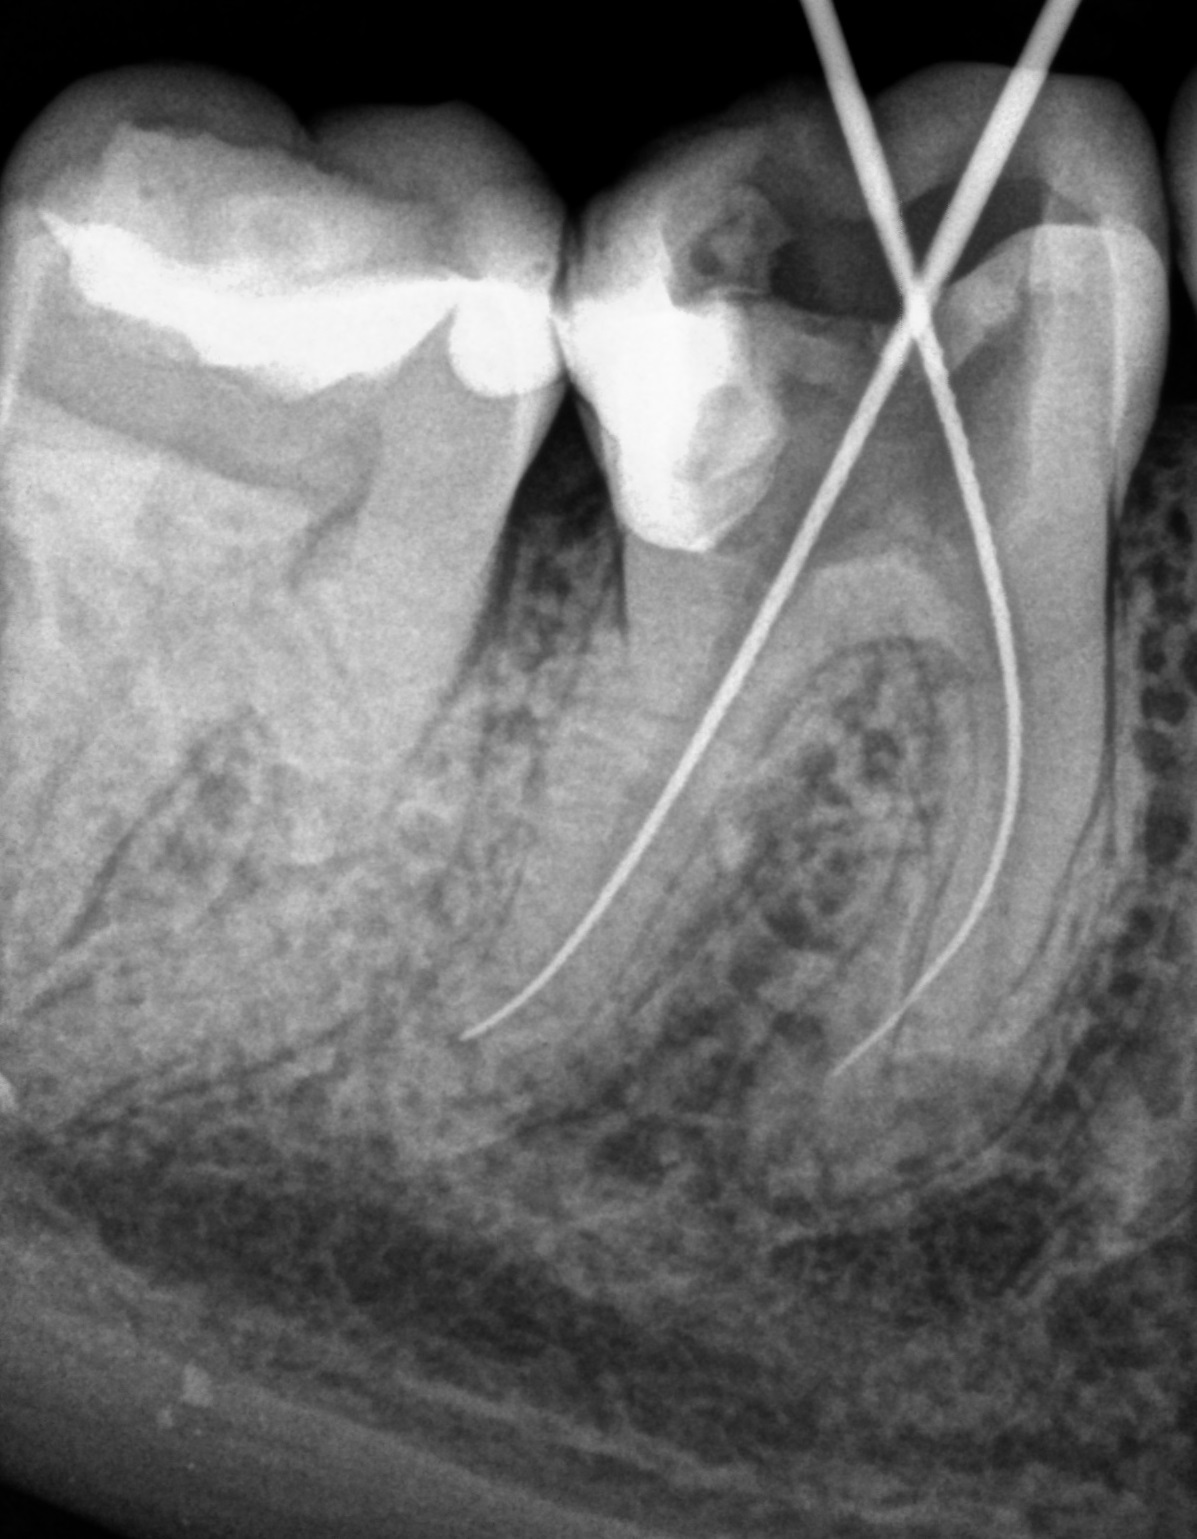

Fast digital imaging of teeth and surrounding tissues that supports safer diagnosis and treatment control.

Our clinic uses modern imaging equipment for teeth and surrounding tissues. Compared with traditional X-rays, it provides an image on screen immediately after exposure.

Digital radiography reduces radiation dose by about 60% and makes image storage easier, so treatment results can be compared even after a longer period of time.